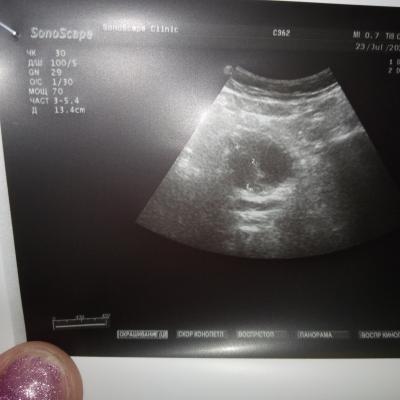

Пожалуйста,можно ли по данным анализам назначить лечение? Какая стадия рака?При отказе на операцию возможен ли прогноз,продолжительность жизни?

анализы отца,пожалуйста подскажите лечение,госпитализироваться отец отказался,боиться.Пожалуйста подскажите лечение,возможно ли оно?